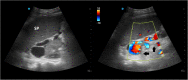

Man with tarry stools